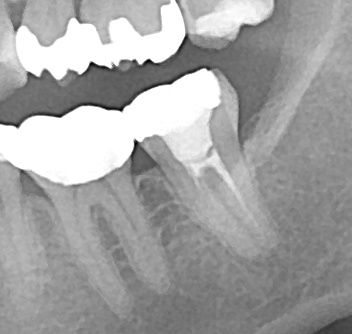

最初のレントゲン

ppprr661

ppprr661.JPG